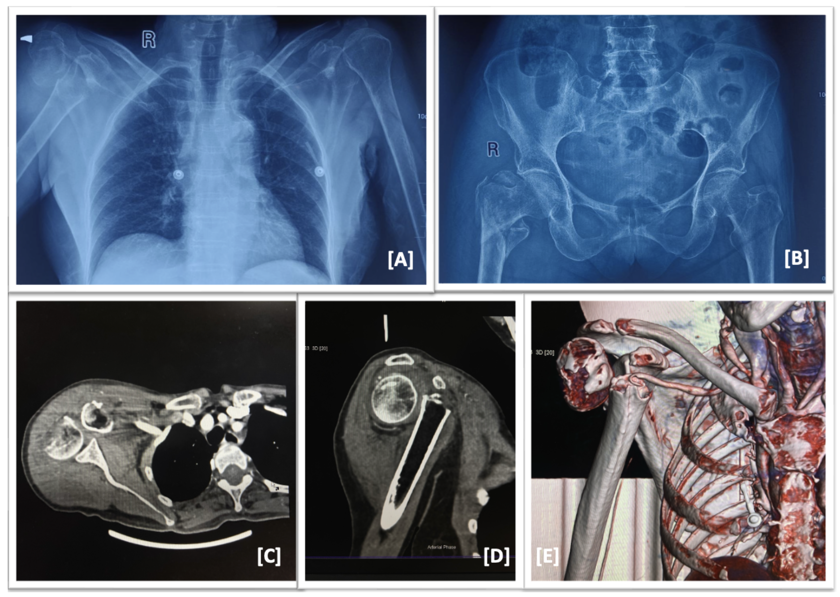

Figure 1: A,B: Plain radiographs of chest and pelvis showing right sided proximal humerus 2

part fracture and proximal femoral fracture (IT fracture, Boyd and Griffin type 3); C,D,E:

Computed tomography with angiogram showing filling defect in 3rd part of subclavian artery.

Radiographs showed a displaced proximal humerus fracture and an unstable intertrochanteric

fracture. But it was the CT angiogram that revealed the real danger — a complete disruption of

the axillary artery, with no distal flow. The upper limb was ischemic, neurologically silent, and

We made a diagnosis of closed displaced 2 part Proximal Humerus fracture right side (Neer 2

part) with axillary artery injury and Global Brachial plexus injury with ipsilateral intert-

trochanteric femur fracture right side (Boyd and Griffin type 3).